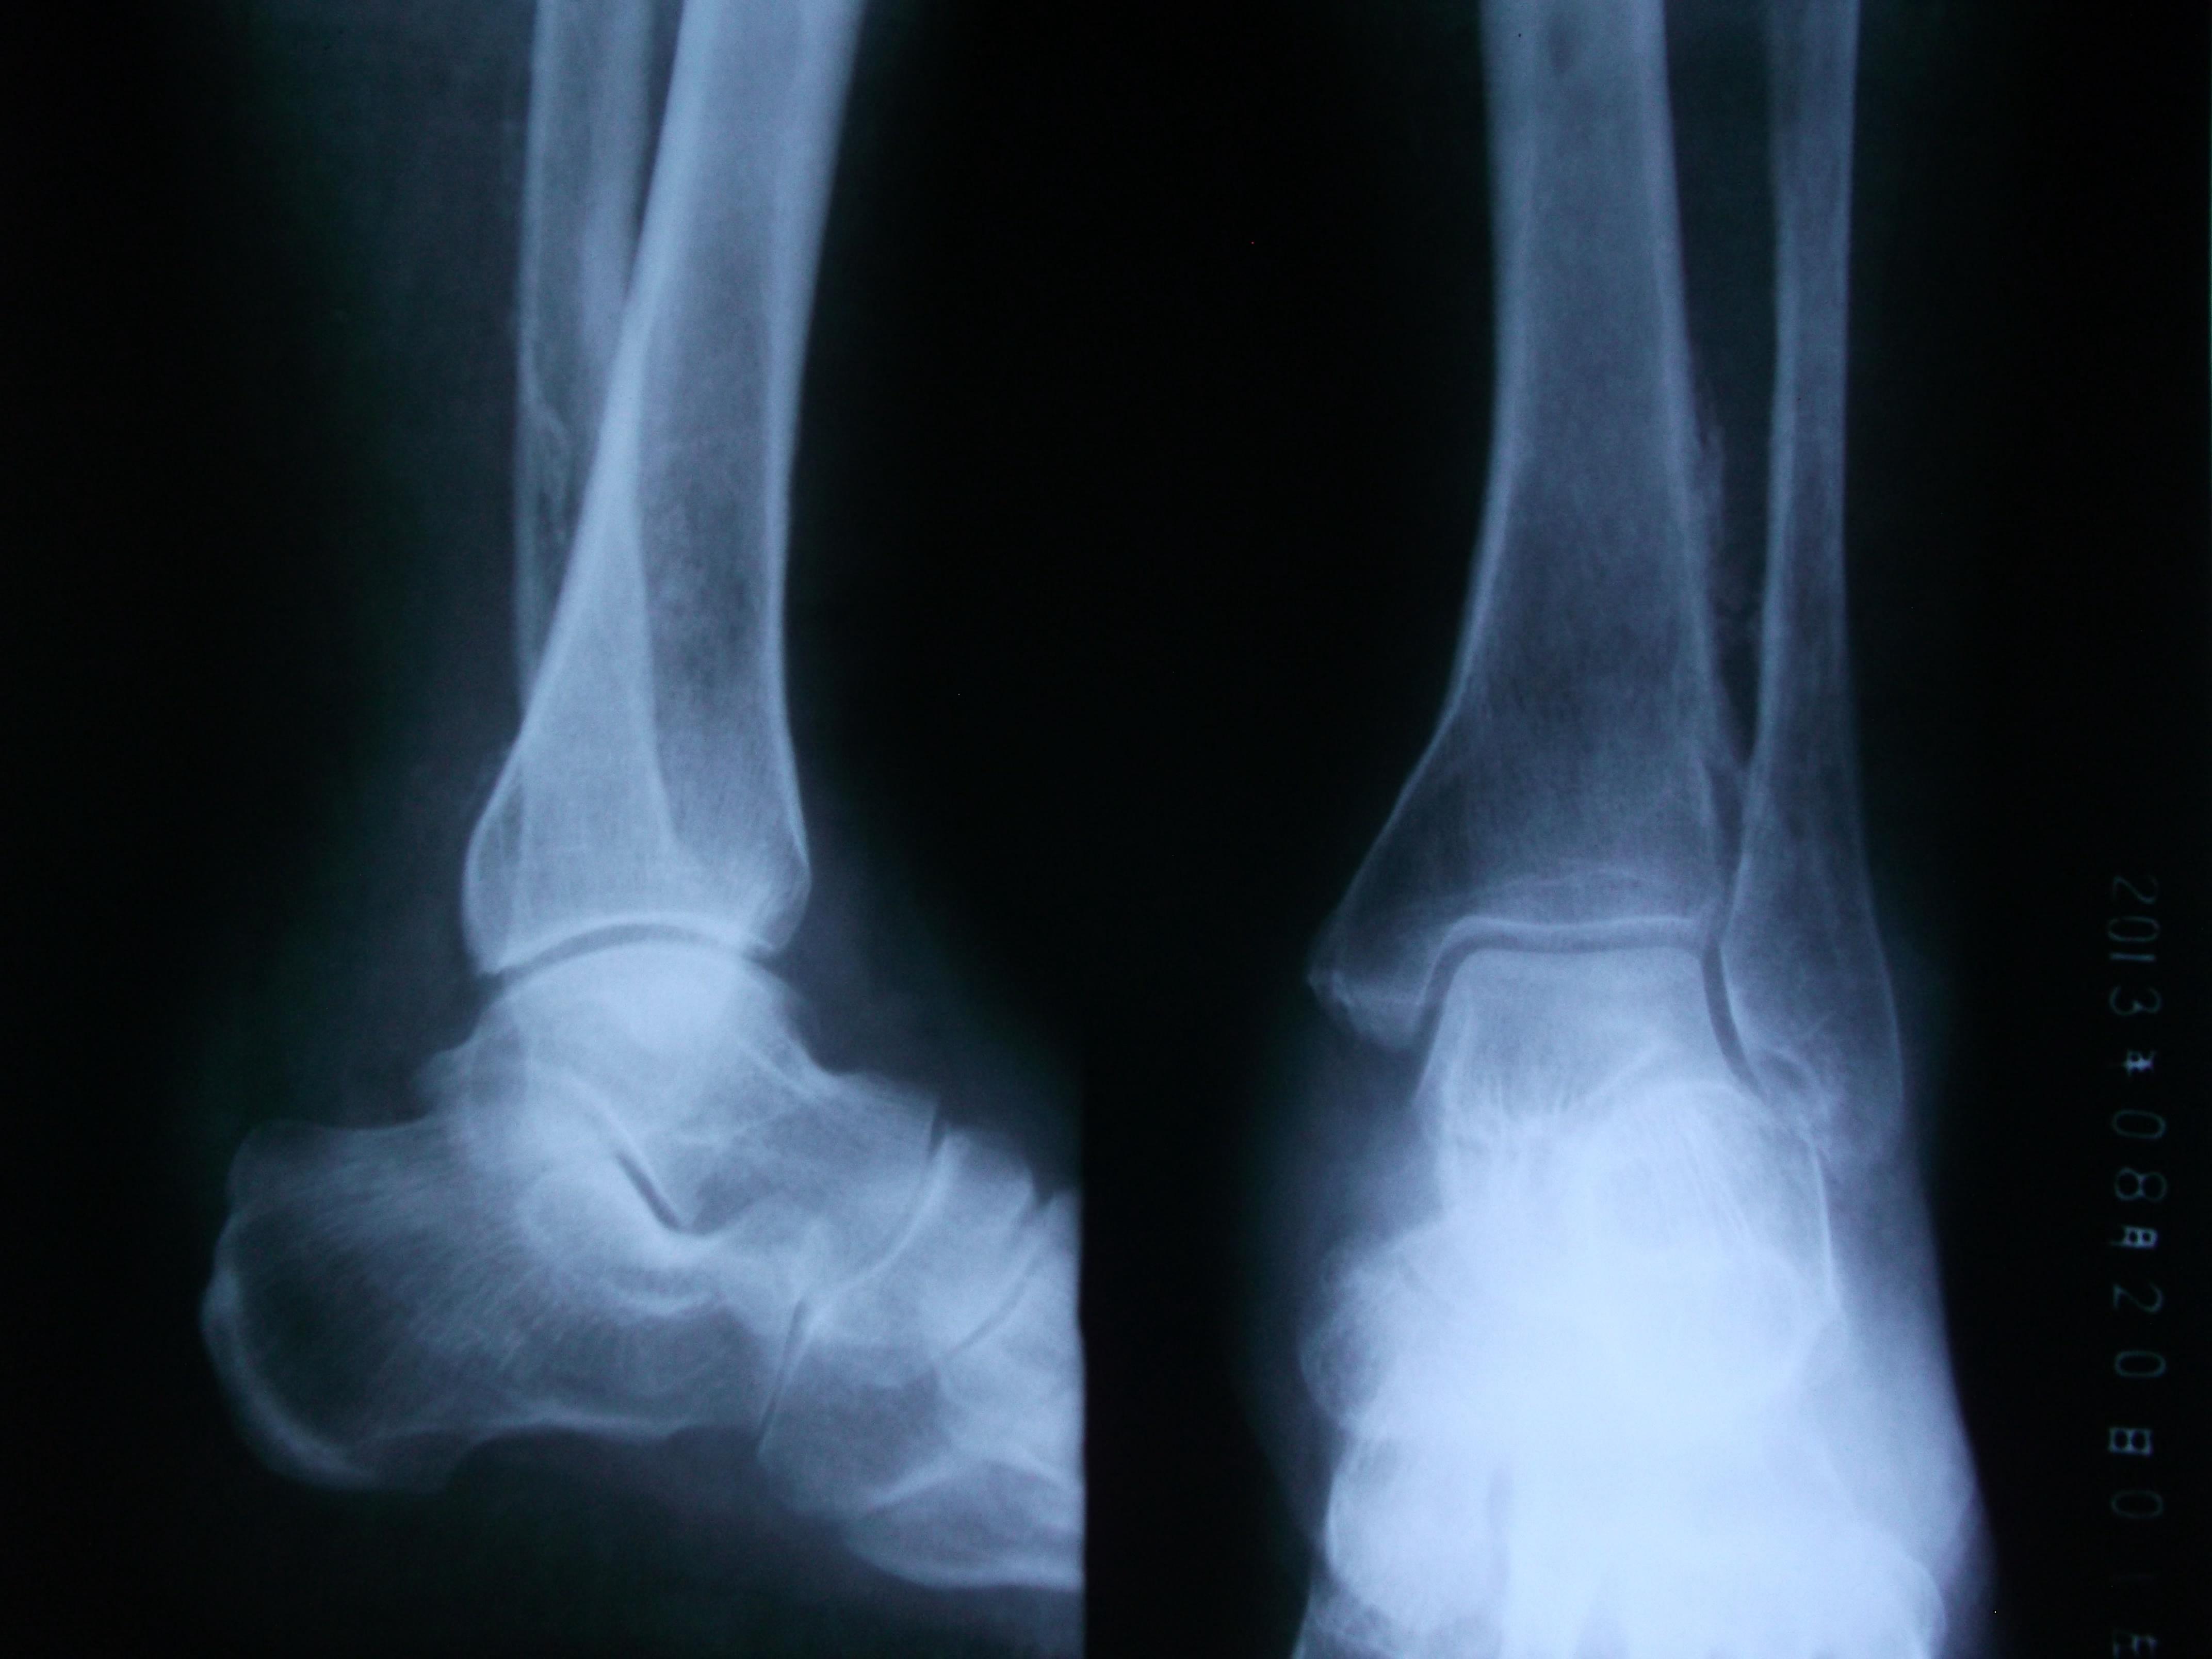

男性,56岁,左小腿静脉曲张十多年了吧,好像做过手术。现在他的整条左小腿肿胀,皮肤发黑,靠近外踝的皮肤出现溃疡。片子不太清楚,因为是基层,条件艰苦没CR。请各位前辈指点下,该患者的左胫、腓骨是什么状况,应该怎样发报告?谢谢!

患者有静脉曲张的病史,现在小腿的肌肉和皮肤都出现缺血坏死的症状;而胫腓骨X光片示胫腓骨下段向对面骨皮质增生模糊,有明显的骨膜反应;也还是考虑骨质长期缺血缺氧所致,类似肺癌所致骨皮质增生的改变。当然,骨髓炎和骨肉瘤等来源骨质本身的疾病不能完全排除。

胫腓骨下段骨皮质模糊,出现葱皮样骨膜反应,骨髓腔稍狭窄,软组织情况不清。考虑急性骨髓炎可能,为排除骨肉瘤,建议CT。